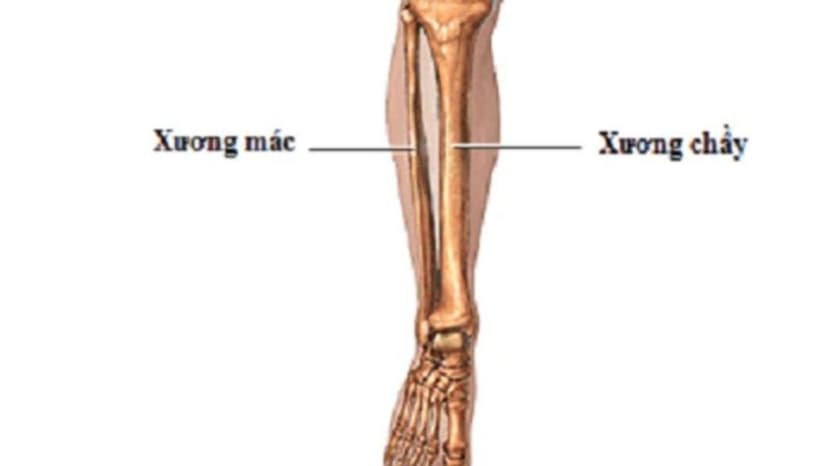

Gãy xương mác là một chấn thương ở vùng cẳng chân không quá nghiêm trọng. Xương mác là xương nhỏ nên rất dễ gãy. Việc gãy xương mác cẳng chân sẽ khiến người bệnh gặp khó khăn trong đi lại, vận động.